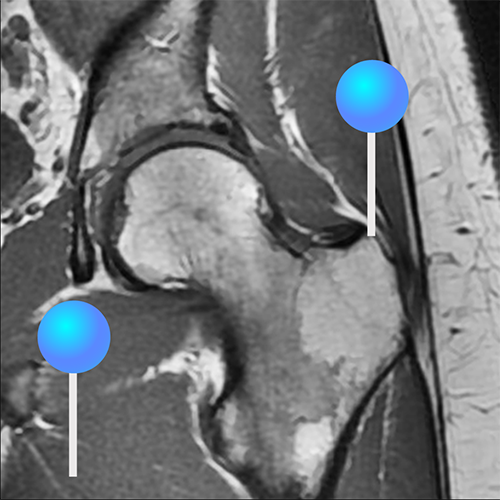

Примеры МРТ тазобедренного сустава при остеопорозе